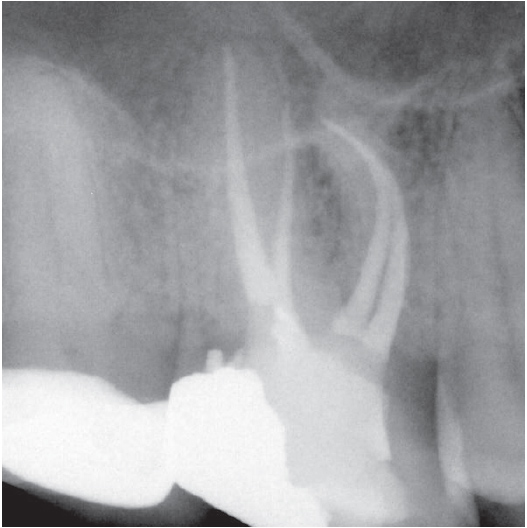

Before

After

Before Root Canal treatment

After Root Canal treatment